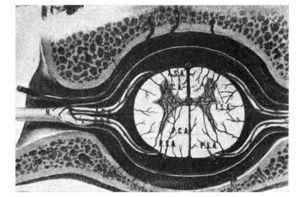

2. Los nervios raquídeos, a su salida de los agujeros de conjunción no están solos, van acompañados de algunas venas y una arteria de mediano calibre, rama de la arteria vertebral. Esta arteria penetra en el agujero de conjunción en un plano anterior al del nervio raquídeo, dando un ramo posterior de capital importancia que cuida de la irrigación del ganglio raquídeo posterior, de las raíces medulares y del mielómero correspondiente para las arterias espinal anterior y espinales posteriores (fig. 1).

Figura 1.Vascularización de la médula y nervios requídeos. Obsérvese la disposición del ramo espinal de la arteria vertebral (SR). (Tomado de Netter).

Este ramo espinal de la arteria vertebral que nos proporcionaba la irrigación de estas importantes estructuras, termina efectuando una anastomosis por inoculación con la arteria correspondiente del lado opuesto, formando así un círculo arterial peridural que contribuye a la vascularización de las vértebras (NETTER).

Dos cosas hay que destacar acerca de esta arteriola, y es que es el único ramo que irriga el ganglio raquídeo posterior y que es terminal en el mielómero correspondiente, como todos los vasos del sistema nervioso central.

El plexo nervioso vegetativo que acompaña a la arteria es muy importante porque procede de la arteria vertebral, rama de la subclavia, que a la emergencia de ésta recibe una tupida red nerviosa originada en el tercer ganglio estrellado.